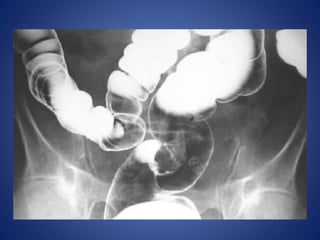

RADIOLOGICAL PICTURE

 Small Bowel Obstruction

- Central distention (GAS)

- Valvulae conniventes

- “Ladder-like dilatation”

- Small diameter

 Large Bowel Obstruction

- Peripheral distention “Picture frame”

- More gross distention

- Haustral indentation & large diameter

In most cases, the abdominal

radiograph will have the

following features:

1. ileated loops of small

bowel proximal to the

obstruction

2. predominantly central

dilated loops

3. dilatation of loops over

3cm

4. valvulae conniventes are

visible

Large Bowel Obstruction